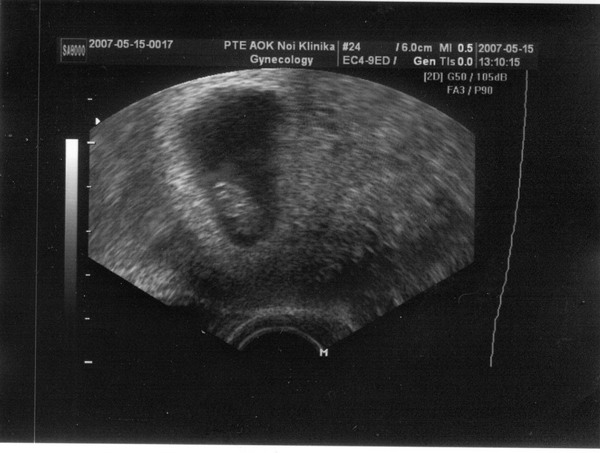

Lara! Szerintem még nem is gratuláltam a kis manóhoz az uh után. Gratulálok most, és vigyázz magatokra nagyon!